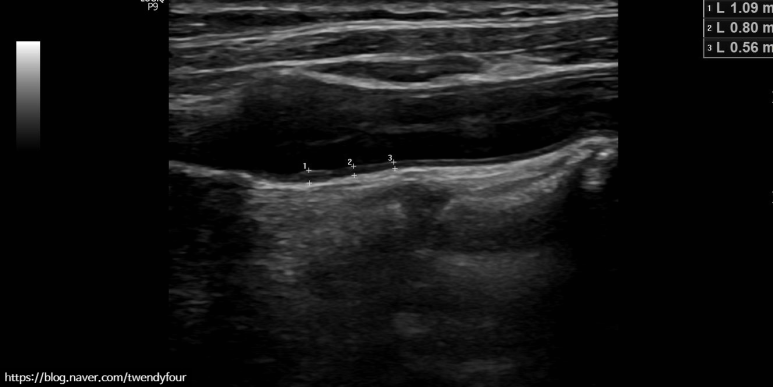

반대편 왼쪽도 경동맥 검사가 똑같이 들어갑니다.

혈관 벽이 두꺼워졌는지 측정합니다.